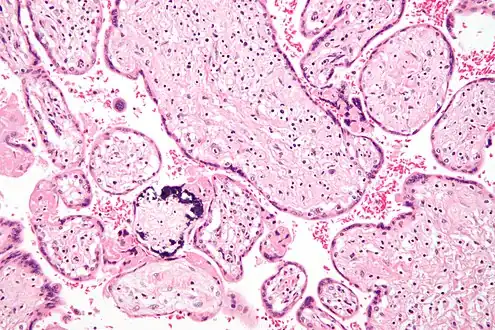

Micrograph of CMV placentitis